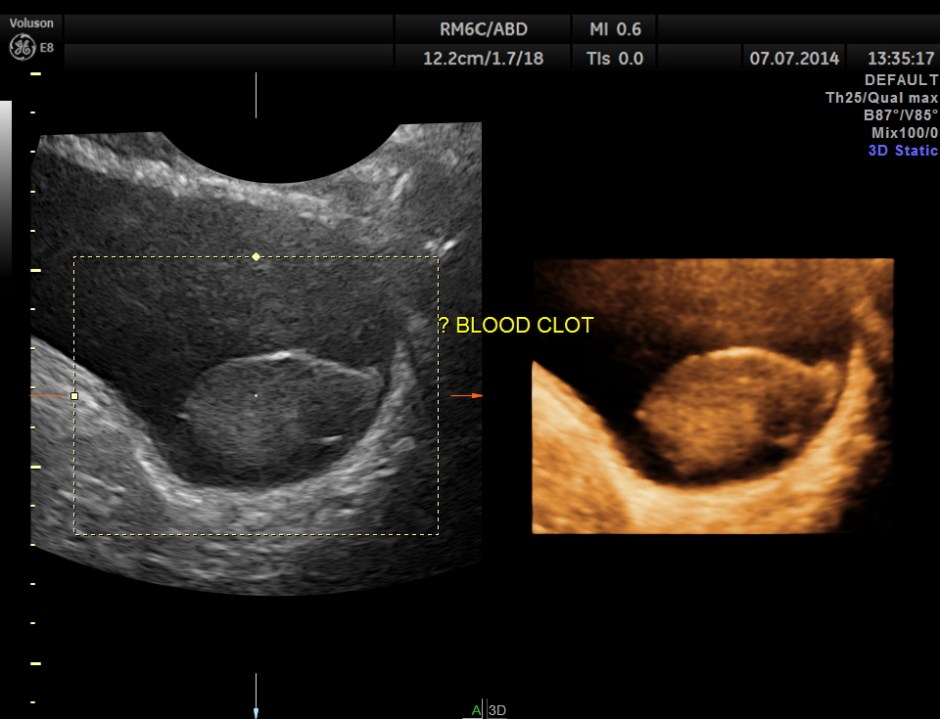

His ultrasound showed the following :

The urinary bladder showed ? mass lesion at first look.

With change of position this ” mass ” was seen to roll within the urinary bladder , suggestive of blood clot.

In this patient the increased vascularity is brought out very well by glass body imaging . Clots of blood seen in the urinary bladder gave the false impression of a mass lesion in the bladder initially.The importance of a dynamic study of turning the patient to the sides should always be remembered.